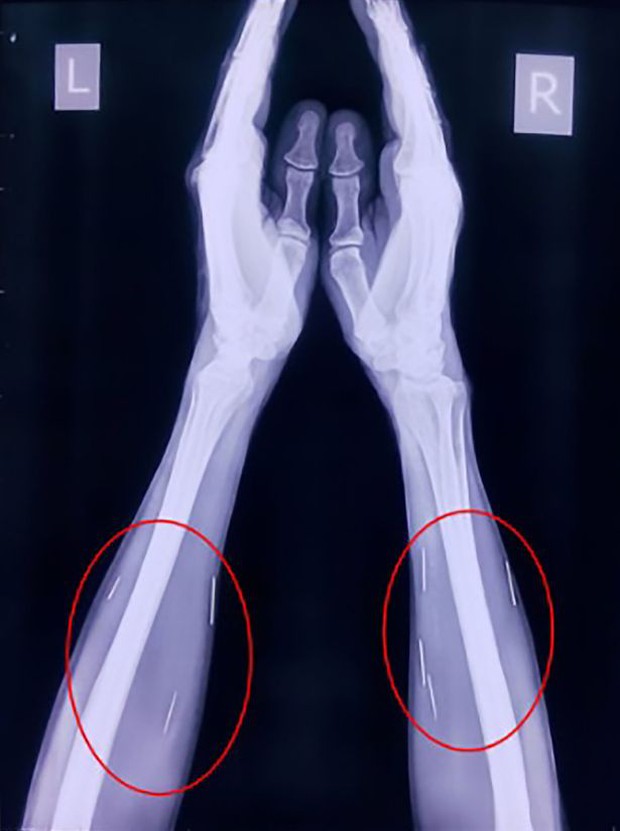

Còn một số cây kim rải rác ở hai bên cánh tay.

Được biết, ông Badrilal Meena, 56 tuổi, sống tại thành phố Kota, miền nam Ấn Độ đến nhập viện tại một bệnh viện ở Mumbai để làm một phẫu thuật thông thường ở ngón chân. Khi tiến hành chụp phim cho ông, bác sĩ đã vô cùng ngỡ ngàng khi phát hiện rất nhiều cây kim bằng kim loại rải rác khắp chân phải. Sau đó, họ kiểm tra thêm các bộ phận khác và tìm thấy 75 chiếc kim ở chân phải, phần họng và hai bên cánh tay.